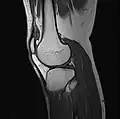

Imaging

MRI

Both anterior cruciate ligament (ACL) and posterior cruciate ligaments (PCL) are hypointense on both T1 and T2 weighted images of MRI. However, some high signal striations are often seen at the distal part of the ACL, making ACL higher intensity than PCL on MRI scans.[20]

-

Knee MRI (PD TSE FS sagittal) -

Knee MRI (T1 TSE sagittal) -

Knee MRI (sagittal TSE FS)

Knee MRI (sagittal T1 TSE)

Knee MRI (coronal T2 TSE FS)

Knee MRI (traverse PD TSE FS)